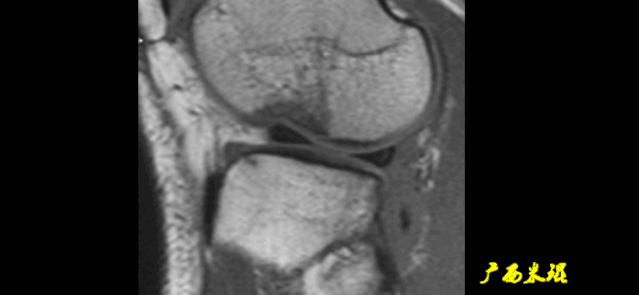

(八)ACL损伤间接征象:

1)ACL撕裂后胫骨前移位出现的一系列改变

2)骨挫伤:

一旦ACL撕裂,胫骨就相对于股骨前移,使股骨外侧髁和胫骨外后方撞击,双方均出现水肿,而且膝关节屈曲的程度决定股骨髁挫伤的部位。

3)沟槽征:

当股骨外髁骨因撞击造成的凹陷深度>2mm时称为沟槽征,代表受到撞击的暴力更大。

4)接吻征:

A.膝关节过伸受伤时,胫骨前部撞击股骨髁前部,形成对称性骨挫伤。

B.如果同时有一外翻力的话,膝关节外侧可出现对称性挫伤,这种对称性骨挫伤称为接吻征。

C.也有人把轴移造成的股骨外侧髁和胫骨外后方水肿称为接吻征。

5)Segond骨折:

-

胫骨平台前外侧撕脱骨折(胫骨平台腓骨尖上方,关节线下方的撕脱骨折),多因为下肢过度内翻加内旋暴力所致。

骨折本身无特殊治疗,但其强烈提示ACL损伤(75–100%)。

6)胫骨前移:

胫骨后缘垂直线位于股骨髁后缘垂直线前方5mm以上。

由于MRI检查时病人为平卧位,胫骨应该因重力而后沉,因此胫骨前移征往往暗示膝关节处于交锁状态。

7)外侧半月板后角裸露征:

外侧半月板后角后缘垂直线位于胫骨后缘皮质垂直线之后方。